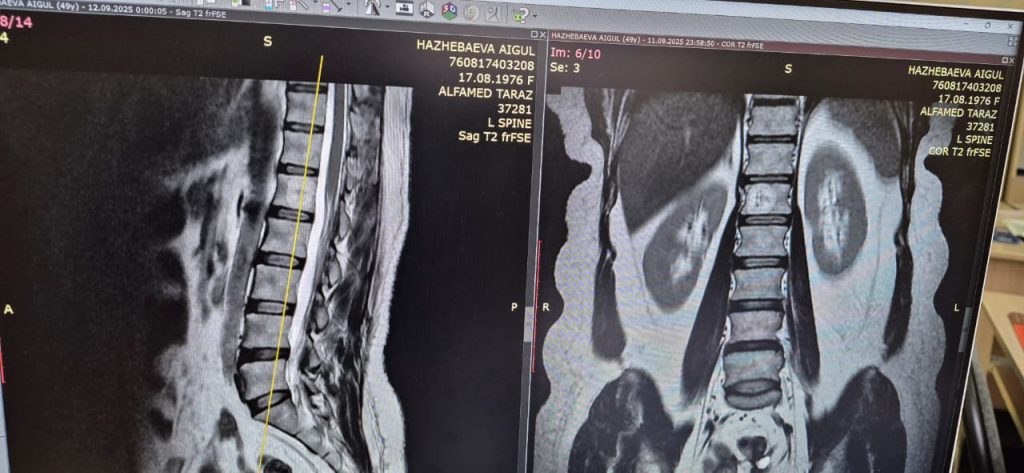

Гемангиома позвоночника

Гемангиома позвоночника — это доброкачественная сосудистая «родинка» внутри позвонка, которую очень часто находят случайно на МРТ: она встречается примерно у каждого десятого человека. Во многих случаях она никак не беспокоит, но иногда опухоль начинает увеличиваться и ослаблять структуру позвонка. Если её не контролировать и не лечить при наличии показаний, со временем могут возникнуть серьёзные осложнения: усиливающаяся боль в спине, прогрессирующее онемение и слабость в ногах, сдавление нервных корешков или даже спинного мозга, а также компрессионный перелом позвонка, который может привести к резкому ухудшению состояния и необходимости срочной операции.

К счастью, сегодня есть современный и безопасный метод лечения — перкутанная вертебропластика. Это малоинвазивная процедура через маленький прокол, при которой в ослабленный позвонок вводится специальный медицинский цемент. Он укрепляет повреждённый участок, останавливает рост гемангиомы и быстро снимает боль. Операция длится около 20–30 минут, проводится без общего наркоза, а вставать можно уже через пару часов.